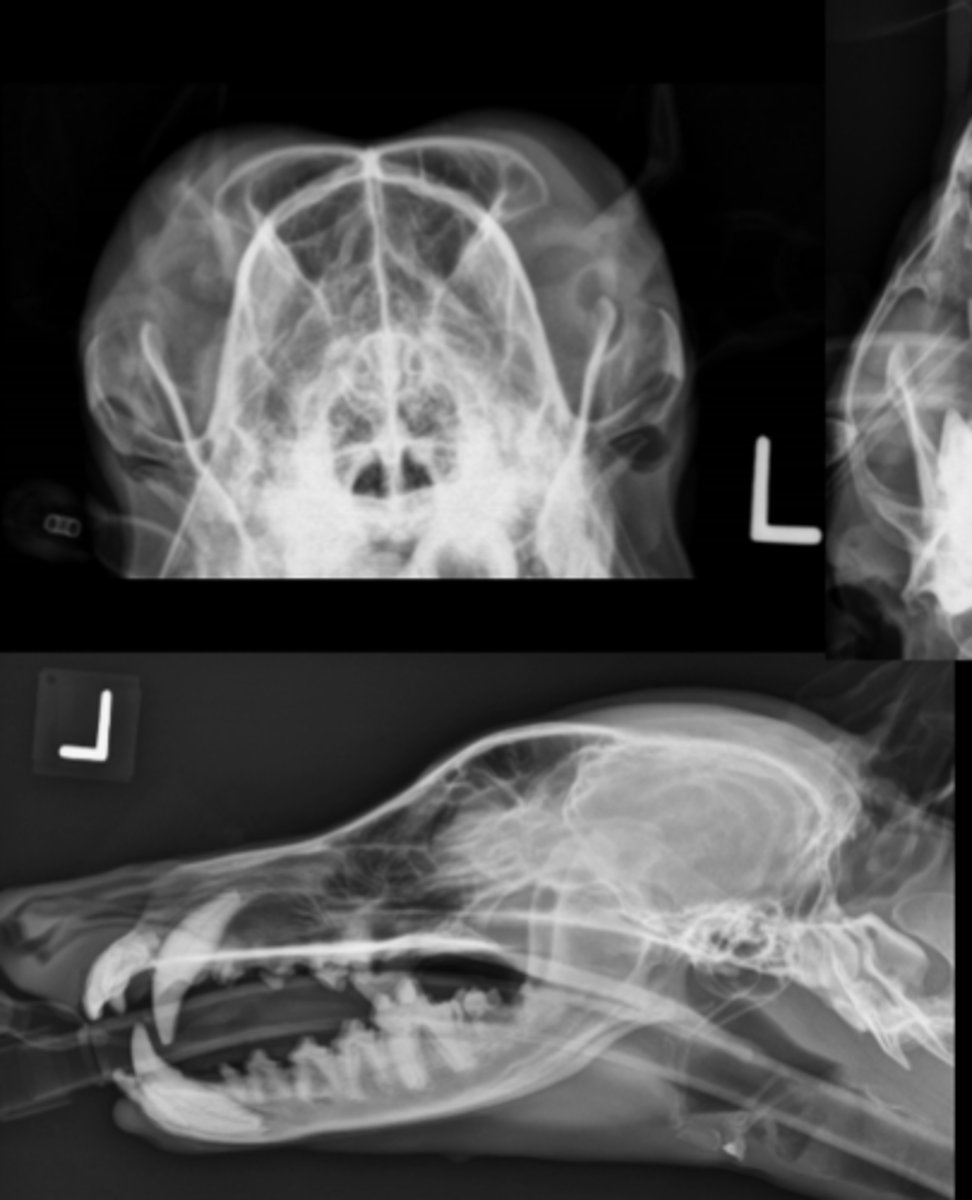

Canine Skull

SM Animal Skull- VD image

• Patient in dorsal recumbency

• Markers to indicate laterality

SM Animal Skull - Rostrocaudal image

• Nose pointed at tube

• Specifically for frontal sinuses